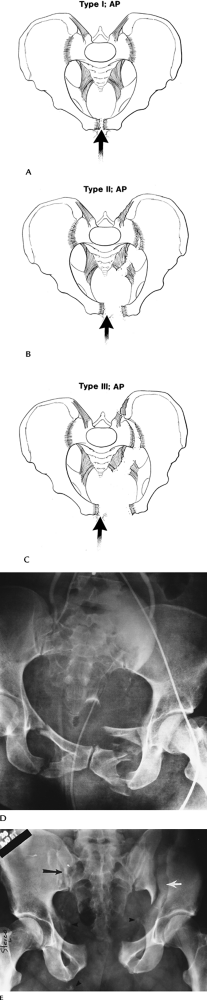

Trauma: Acetabular Fractures—Simple

-

Mechanism of injury—lower extremity trauma with force directed to the femoral head.

Fractures involve posterior acetabulum if hip flexed. Posterior dislocation may occur.

Transverse and anterior fractures occur with lateral blow to greater trochanter.

AP and Judet views may detect injury. CT

with coronal and sagittal reformatting is useful to evaluate and

characterize subtle fractures and the joint space involvement. -

Complications—minor, or arthrosis in later years.

![]() |

FIGURE 4-8 (A) Judet view of the hip demonstrating and undisplaced central acetabular fracture (curved arrow). (B) CT image demonstrating an uncomplicated central acetabular fracture (arrow).